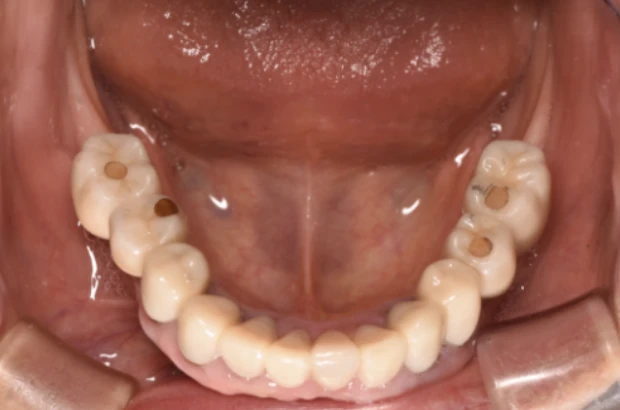

症状を詳しく見る: 症例7

主 訴

何度か入れ歯を作りなおしたが合わない

治療期間

24ヶ月

治療内容

インプラント7本、上顎自費義歯、セラミックCK8本

費 用

3,020,000円